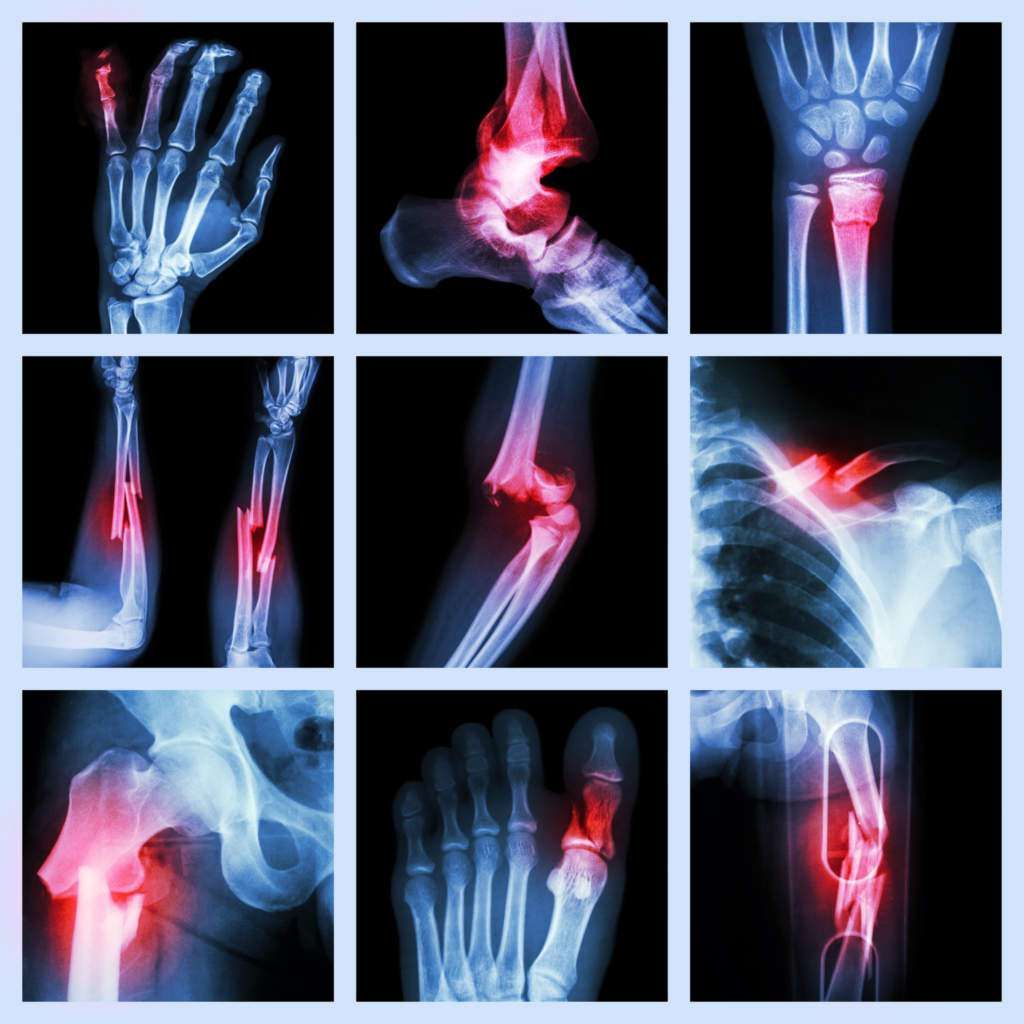

What types of complex fractures do you treat?

Complex Fracture Treatment in Malakpet We manage pelvic fractures, acetabular fractures, intra-articular fractures, compound fractures, comminuted fractures, limb fractures, nonunion/malunion cases, and periprosthetic fractures.

🩺 What Causes Complex Fractures?

Complex fractures occur due to high-impact injuries or weak bones. Proper evaluation helps plan the right treatment.

3. Injury Complexity

- Multiple bone fragments

- Joint-involving fractures

- Pelvic or multi-bone injuries